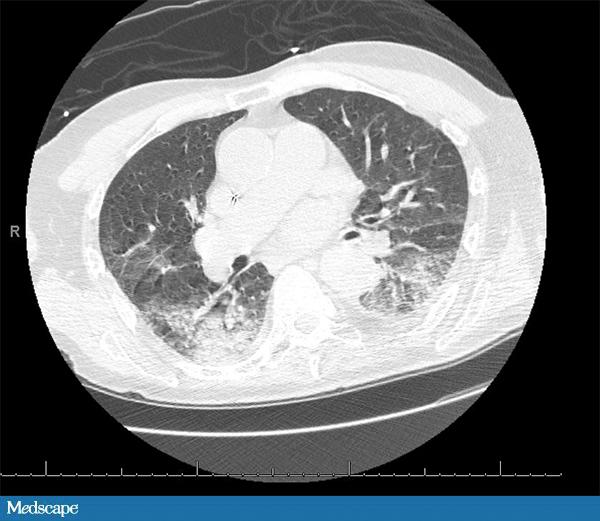

89 岁男性,有房颤、癫痫、痴呆病史。家属发现其昏迷并伴有右侧上下肢震颤,送至急诊科。患者的抗癫痫药于发病前一天吃完。体查示患者低烧(37.9°C),血压、心率、呼吸均正常。就诊时仍处于癫痫发作状态,遂予劳拉西泮解痉。患者白细胞 20,700/µL,中性粒细胞 77%。血红蛋白和血小板均正常。肌酐轻度升高(1.5 mg/dL)。心电图示房性节律,ST-T 波广泛性改变。肌钙蛋白 >40 mg/dL。CT 示“可能由吸入引起的双肺实变”。患者收入重症监护室。予头孢曲松控制肺炎,当晚换成舒巴坦。次日早晨,患者情况稳定,白细胞恢复正常。此时应如何进行下一步处理?

患者的临床症状和 CT 均提示轻度吸入性非细菌性肺炎(编者注:pneumonitis,这里应关注与 pneumonia 相区分,前者通常指吸入性的非感染性的炎症,比如胃液腐蚀性的;后者 pneumonia 常指感染性的肺炎,下文中同),这种情况可以发生于意识丧失期间。患者最主要的问题是心脏,白细胞升高很可能是心梗(肌钙蛋白阳性)造成。无发热且无明显的 CT 发现提示肺炎的可能性不大。另外,如果是常规感染性肺炎,白细胞不太可能这么快恢复正常。

吸入性非细菌性肺炎(pneumonitis)是吸入返流的胃内容物造成的,需进行气道管理。预防性使用抗生素不会对病情有利,反而会筛选出更加耐药的微生物。吸入性非细菌性肺炎是一种化学炎症反应,而通常所说的吸入性肺炎(pneumonia)是一个感染过程,二者常常混淆。通常所说的吸入性肺炎由吸入口咽部的分泌物导致,常见于神经性吞咽困难、胃和食管连接异常或上呼吸消化道解剖形态异常的患者。和吸入性非细菌性肺炎不同,通常说的吸入性肺炎需要抗生素治疗。我们可以通过发热、脓性分泌物和呼吸窘迫(呼吸急促、缺氧)与否对二者进行鉴别。